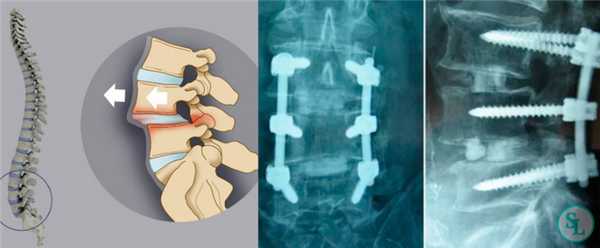

TLIF является наиболее эффективным методом лечения пациентов с нестабильным позвоночно-двигательным сегментом позвоночника. Дискэктомия с последующей установкой межтелового кейджа через одно из межпозвонковых отверстий, путем резекции сустава между позвонками, приводит к стабильности передней колонны и создаёт условия для формирования костного блока. Используемый костнопластический материал для создания сподилодеза, заполняет свободные пространства вокруг межтелового стабилизатора и внутри него. Межтеловая стабилизация дополняется транспедикулярной фиксацией, что увеличивает сегментарную стабильность позвоночно-двигательного сегмента и приводит к формированию костного блока позвонков в 98% случаев по данным различных авторов. Цель данной методики — декомпрессия невральных структур и создание косного блока между позвонками.

- Односторонний доступ к межпозвонковому диску.

После скелетирования позвонков устанавливается ранорасширитель. Доступ к межпозвонковому диску осуществляется с той стороны, где у пациента имеется клиническая картина радикулопатии. Если клиники радикулопатии нет, то сторона доступа значения не имеет. На примере дегенеративного спондилолистеза L4 позвонка будет разобран метод стабилизации. При помощи костных кусачек и долота удаляется межпозвонковый сустав L4-L5 справа. Рисунок 6. На противоположной стороне временно тампонируют рану после скелетирования.

После резекции межпозвонкового сустава становится виден корешок L4, межпозвонковый диск и с медиальной части дуральный мешок. Далее выполняется тщательная коагуляция расположенных в области межпозвонкового отверстия эпидуральных сосудов. Дуральный мешок аккуратно смещается медиально и начинается этап дискэктомии и межтеловой стабилизации.

Скальпелем рассекается фиброзное кольцо межпозвонкового диска, далее при помощи кюреток и кусачек Керрисона выполняется дискэктомия. С замыкательных пластинок тел позвонков удаляется хрящевая часть при помощи кюреток.

В подготовленное межтеловое пространство устанавливается пробный межтеловой спейсер. Высота и длина пробного спейсера, плотно установленного в межтеловое пространство, соответствуют кейджу, который будет имплантироваться. Выполняется рентгенологический контроль в боковой проекции.

Перед установкой кейжда межтеловое пространство заполняется аутокостью полученной на предыдущих этапах операции или аллокостью. Пространство кейджа так же заполняется ауто- или аллокостью. Под рентгенологическим контролем выполняется установка межтелового импланта: PEEK или титановый кейдж имеющий форму межпозвонкового диска.